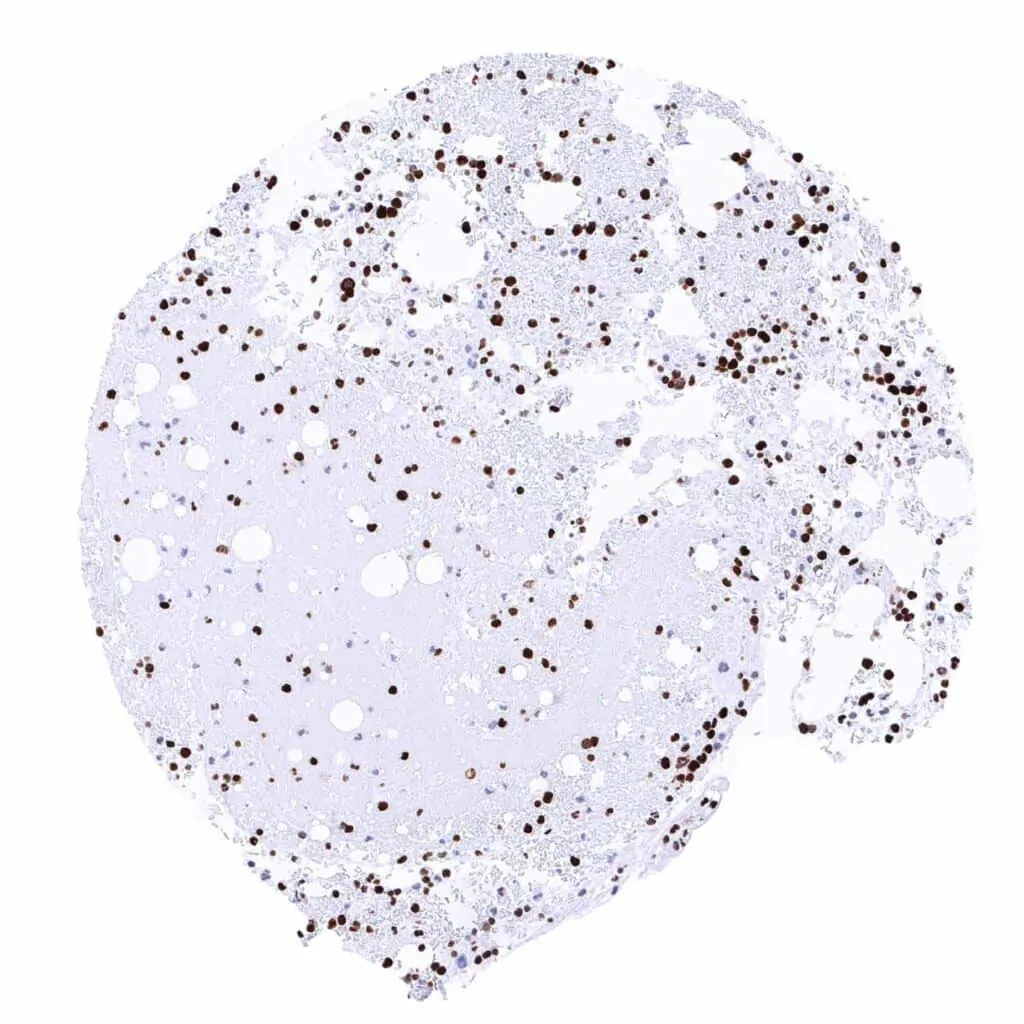

Bone marrow – Moderate to strong MCM2 staining in most bone marrow cells

Lymph node – Many lymphocytes are MCM2 positive. Strongest MCM2 staining occurs in most cells of germinal centres and in scattered individual cells of the interfollicular zone

Spleen – A strong MCM2 positivity occurs in scattered cells of all compartments

Thymus – Strong MCM2 positivity of most cells of the thymic cortex